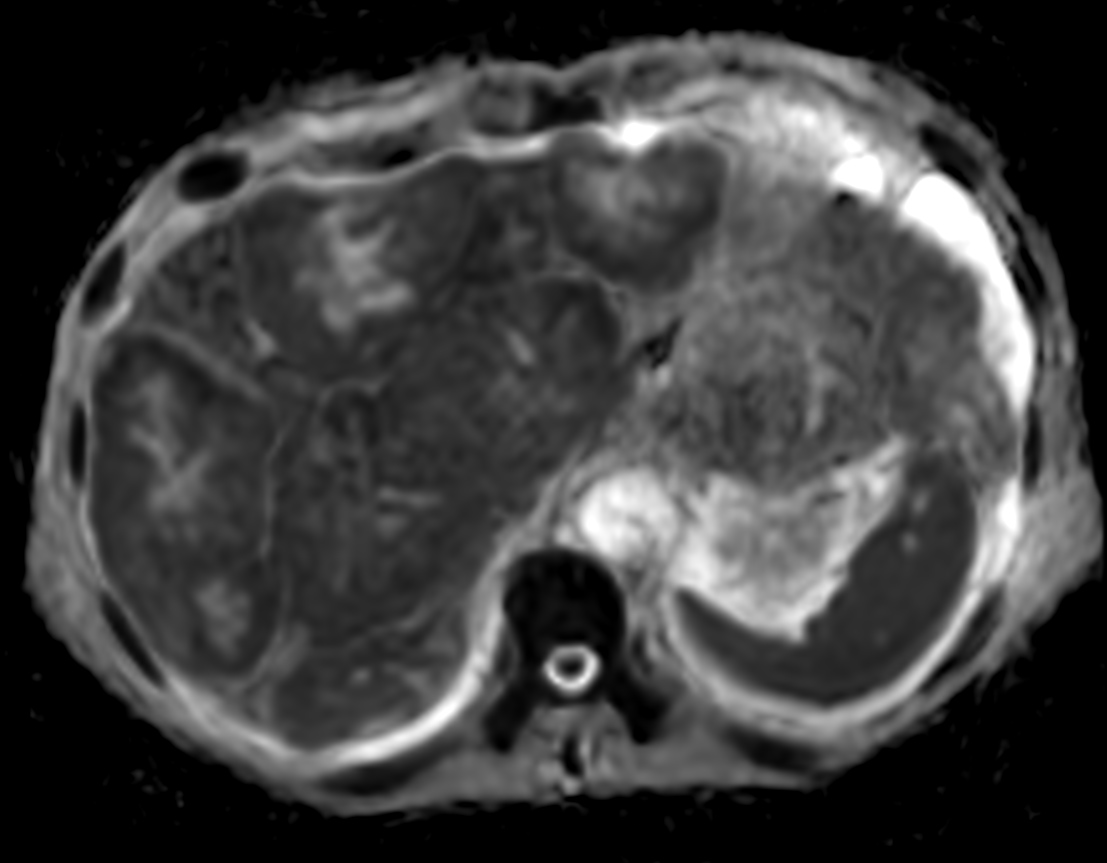

Patient with liver metastasis. The ExamCard includes techniques for efficient fat-free imaging over large field-of-views (mDIXON XD), a procedure for non-invasive liver fat quantification (mDIXON Quant), a multi-phase contrast-enhanced sequence (4D FreeBreathing) to improve imaging confidence and Compressed SENSE to accelerate the entire exam.

DWI b1000